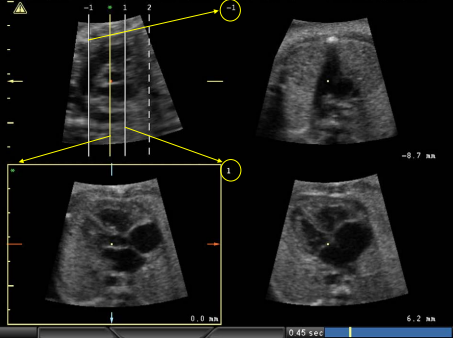

بسیاری از متخصصان مجرب مراقبت های بهداشتی، اعم از ماما، سونوگرافی، متخصص زنان و زایمان، پریناتولوژیست یا رادیولوژیست، می توانند قلب جنین را با درجه بالایی از دقت تشخیصی در طول ارزیابی سونوگرافی مامایی ارزیابی کنند. بسته به ماهیت ضایعه قلبی مشکوک، اکوکاردیوگرام را می توان فردی کرد. حداقل شامل معاینه کامل نمای چهار حفره ای، هر دو مسیر خروجی شریانی، سه رگ و نمای نای و ارزیابی بازگشت وریدی ریوی است. آزمايشگر بايد روابط آناتوميکي و خصوصيات جريان عملکردي را از طريق آناليز سيستماتيک حوزه هاي زير تاييد کند:

این ویژگی های تشریحی معمولاً با استفاده از نماهای عرضی ارزیابی می شوند، اگرچه در صورت لزوم از صفحات اسکن ساژیتال نیز استفاده می شود. با این حال، تا زمانی که ساختارهای قلبی مربوطه به طور رضایت‌بخشی تجسم می‌شوند، دیدگاه‌های خاص اهمیت کمتری دارند. سونوگرافی داپلر رنگی یکی از اجزای مهم اکوکاردیوگرام جنین است. اگرچه سونوگرافی داپلر طیفی ضروری نیست، می توان از آن برای مشخص کردن بیشتر ماهیت و شدت اختلالات مشکوک جریان استفاده کرد. سونوگرافی داپلر با موج پیوسته گاهی برای تعیین کمیت جریان با سرعت بسیار بالا در دریچه های تنگی یا ناکارآمد ضروری است. گاهی اوقات، ممکن است تکنیک های پیشرفته ای برای ارزیابی عملکرد قلب جنین با استفاده از اندازه گیری کسر جهشی بطنی، حجم ضربه، برون ده قلبی، فواصل مکانیکی PR، شاخص های Tei و پارامترهای فشار بطنی مورد نیاز باشد. سونوگرافی حجمی یک رویکرد تکمیلی را برای آنالیز ضایعات پیچیده قلبی امکان پذیر می کند و همچنین ممکن است مزایای مهمی را برای کاربردهای پزشکی از راه دور، آموزشی و تحقیقاتی ارائه دهد.

ناهنجاری های مشکوک را می توان با استفاده از چندین روش تصویربرداری ارزیابی کرد، اگرچه معاینه را می توان برای ناهنجاری های خاص قلبی جداگانه ارزیابی کرد . سونوگرافی در مقیاس خاکستری بلادرنگ و تکنیک های سونوگرافی داپلر مکمل (به عنوان مثال طیفی و رنگی) اغلب استفاده می شود. اکوکاردیوگرافیM-mode و سونوگرافی داپلر نیز ابزارهای مهمی برای تجزیه و تحلیل دیس ریتمی قلب جنین هستند. نتایج اضافی، از سونوگرافی سه بعدی (3 بعدی) و 4 بعدی، ممکن است اطمینان تشخیصی را برای توصیف دقیق برخی از ضایعات پیچیده افزایش دهد.